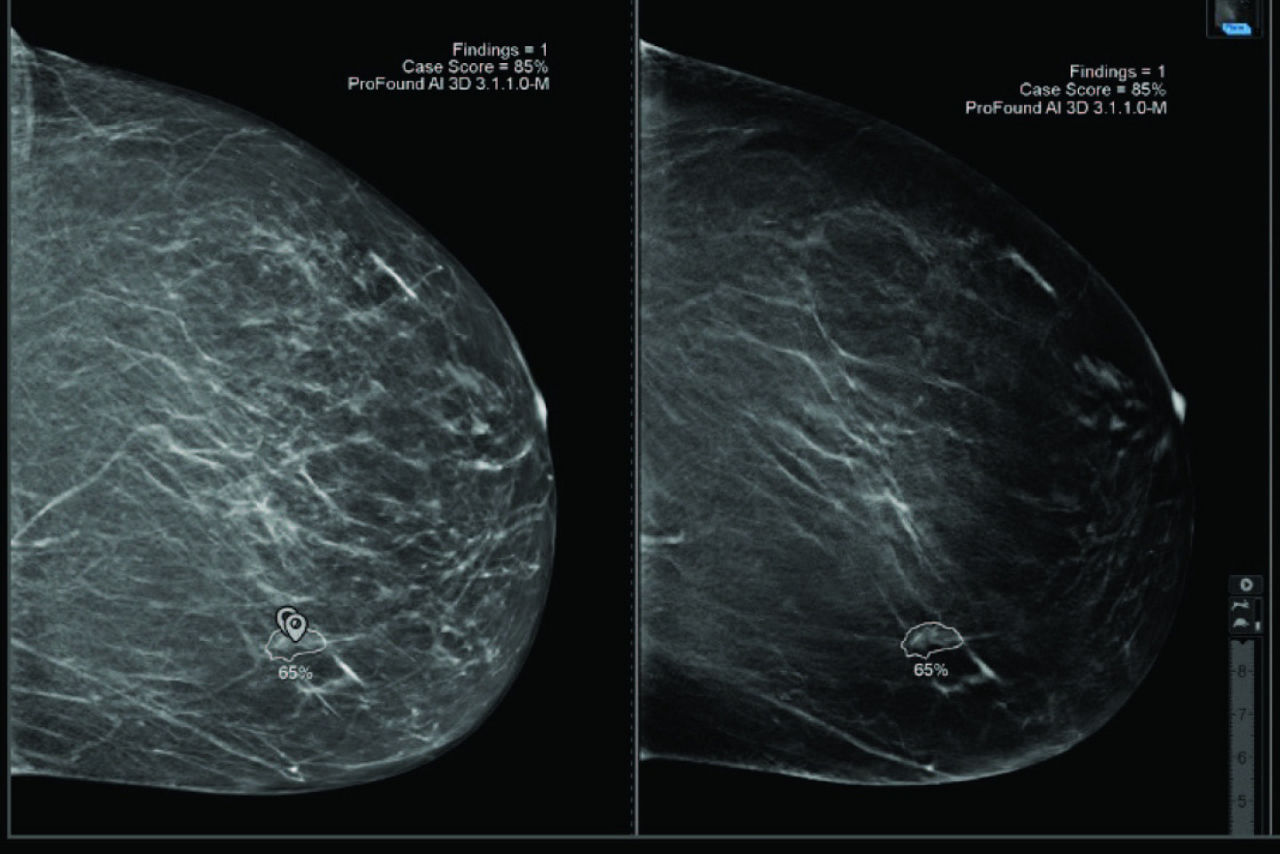

ProFound AI® for DBT

Trained with one of the largest available 3D image datasets, ProFound AI provides radiologists with crucial information, such as lesion Certainty of Finding and Case Scores, which assists in prioritizing caseload, clinical decision-making and may help to reduce physician burnout3.

iCAD reader study shows that reading with ProFound AI:

• Increases reader sensitivity by 8%. 4

• Increases reader specificity by 6,9%. 4

• Decreases reading time by up to 52% compared to without. 4

Easy navigation between the V-Preview and the slices containing the AI markers.